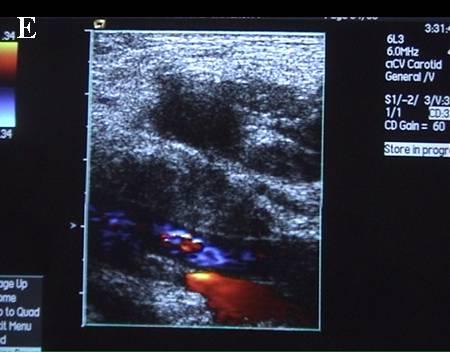

A 连接三联管及穿刺针准备 B 超声引导下注射针进入瘤腔底部(箭头处) C 经注射针注入盐水出现超声频闪现象; D 远端瘤腔内血栓逐渐形成; E 远端、近端瘤腔内血栓完全形成; F 术后足背动脉血流良好. 国内首家开展,例数最多,疗效肯定。此技术在全国推广应用。处于全国领先水平。